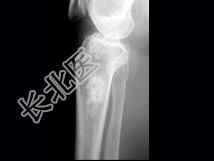

- 单项选择题女,年龄47岁, 膝关节疼痛6月余,曾服用泼尼松(服用时间5个月), 有骨性关节炎史,结合图像, 最可能诊断是 ( )

A、慢性化脓性骨髓炎

B、骨梗死

C、恶性骨肿瘤

D、内生软骨瘤

E、骨纤维结构不良